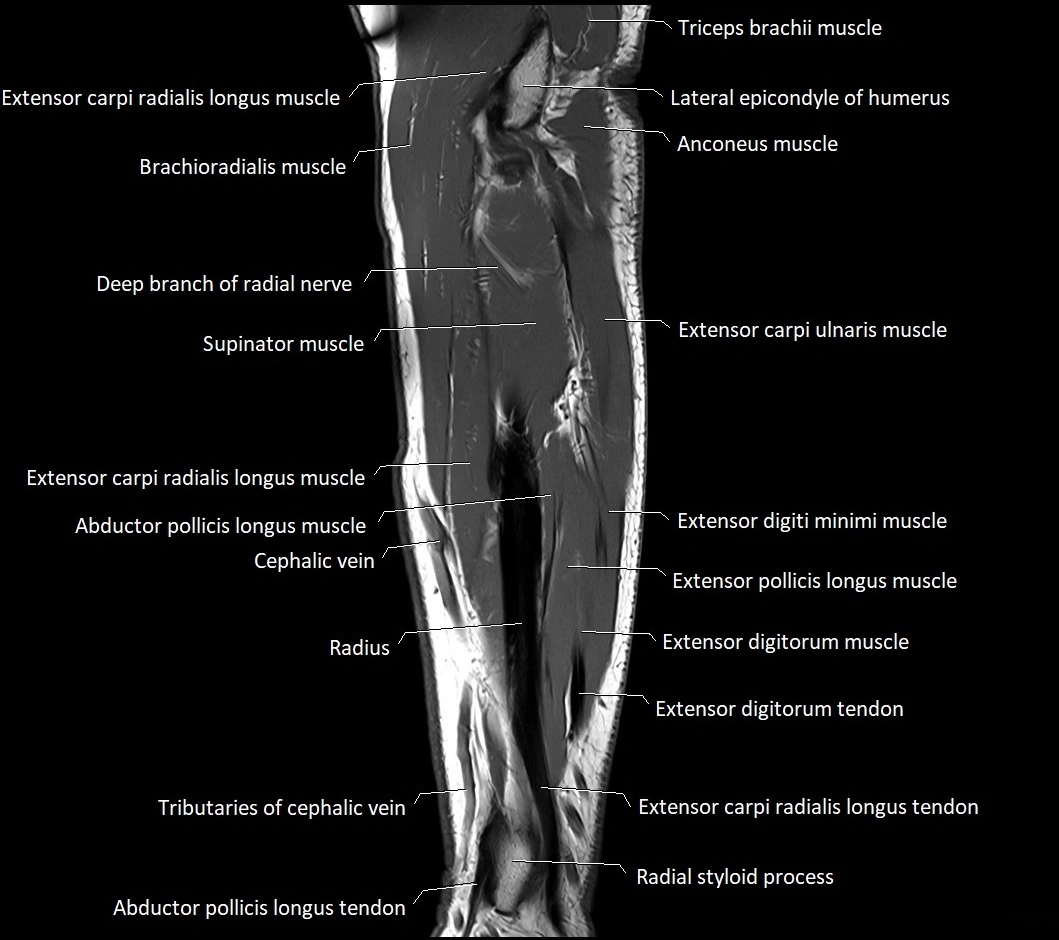

MRI images

image